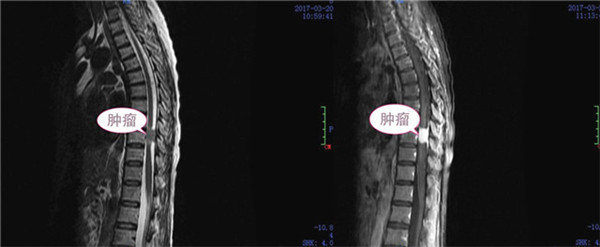

患者于3个月前开始出现双下肢麻木、活动乏力,1周以来呈进行性加重, 并迅速发展至截瘫,大小便失禁。据了解,患者3个月前始已出现身体不适,但未及时汇报,自以为“练功”可以解决问题,而致病情拖延,监狱干警和管理人员及时发现了她的病情,并将她转送广西监狱总医院(南宁茅桥中心医院)就诊,经胸椎核磁共振检查,发现患者胸10水平椎管内占位至椎管狭窄、脊髓严重受压变细,因该院专科治疗水平有限,便紧急联系一附院,外六科主任张高炼教授前往会诊后建议转至一附院。

对于这样一位病情较重而又在服刑期间的特殊患者,一附院开通绿色通道救治及检查,外六科将有限病房腾出一间作为专用,以利患者医疗管理及狱警工作人员值守。针对患者病情,科主任张高炼组织全科进行了疑难病例分析和术前讨论,根据患者症状,结合影像学资料,意见椎管内占位病变为脊膜瘤的可能性较大,因肿瘤造成胸9、10水平脊髓完全受压,有明确手术指征且必须尽快手术切除。经告知患者及家属病情并与监狱领导汇报,大家都期望尽快手术治疗。

脊膜瘤血供丰富,胸椎椎管官腔较为狭窄,手术既要完全切除肿瘤又要避免损伤脊髓功能,治疗存在一定难度和风险,为此科室详细制定了手术方案,做好风险评估和应对预案,经及时而充分的术前准备,入院第三天(3月23日),手术如期进行,以张高炼主任为主刀的手术团队,术前予X线定位,并用亚甲蓝准确标记切口部位。在对患者实施麻醉后,经后正中入路,行胸9、10脊膜瘤切除术,在显微镜下仔细将正常脊髓组织与肿瘤仔细分离,操作轻、准、稳缺一不可,最终将脊膜瘤连同侵犯硬脊膜切除,并用人工硬脊膜严密修补。整个过程顺利,完整切除肿瘤,脊髓及神经保护完好。术后第一天,患者病情明显改善,皮肤感觉麻木平面明显下移,由原来的脐水平降至趾骨联合水平,双下肢肌力及大小便功能逐渐恢复;术后病理确诊脊膜瘤。术后三天,按监狱医院管理方面的要求,予转回茅桥中心医院继续康复治疗。

术前肿瘤影像

术后肿瘤影像